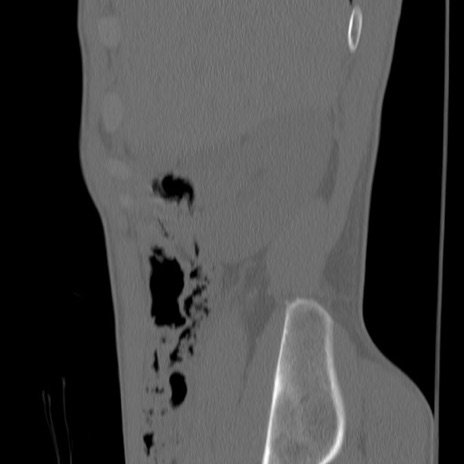

症例3 腰椎CT(矢状断像)

【症例】30歳代男性

【主訴】腰痛

【現病歴】本日旅行先で観光中に、友人と衝突し転倒し受傷。

【身体所見】麻痺なし、右下腿内側前面外側、左下腿内側に知覚鈍麻・しびれ

異常所見と診断は?

腰椎CT